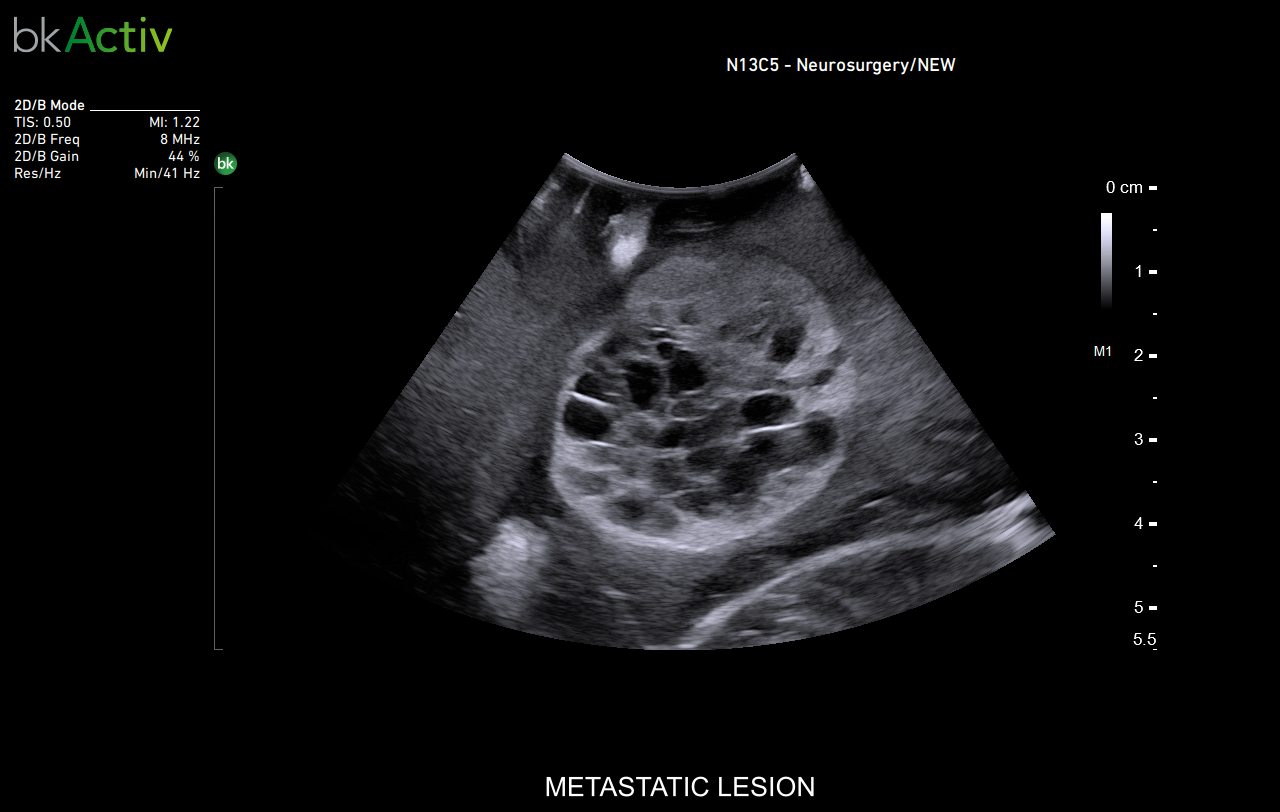

Neurosurgery and Spine

Enhanced Visualization

Improved algorithms that automatically allow uniform image resolution, greater details around lesion borders and at larger depths, and enhanced penetration, spatial resolution, and near field image quality.